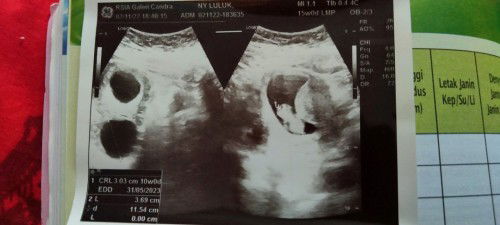

awalnya usg saat 8w baru kelihatan kantong kehamilan belum ada janin alhamdulillah usg saat 10w kelihatan janin&detak jantung janin normal tapi tiba-tiba terdeteksi kista 3cm ada yang punya pengalaman yang sama gak ya? usia kandungan kalau menurut hpht 15minggu tapi di usg baru 10minggu kira-kira mana ya yg lebih benar? ##seriusnanya #bantusharing #ingintahu #firstmom #pleasehelp #firstbaby